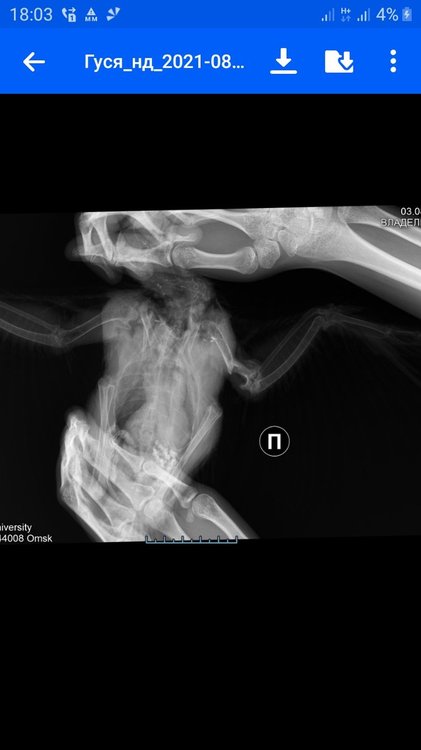

Скажите, какой должен быть рентген? В двух проекциях или какой???

Рнтген - для начала прямая ВД проекция. Как птицу раскладывать- есть на форуме. В позе Христа. Так быдет возможно визуализировать сустав.

Как у меня на прямой проекции в начале темы, как я поняла.

Произошла ужасная ситуация. Короче, в одной клинике отказали под непонятным предлогом. В другой сделали так .... что просто кость вылезла... и вся эта шишка, просто кусок кости отпал... я короче просто в шоке, там теперь просто открытая кость или я даде не знаю как сказать. Надо ставить уколы, чтобы там не пошла чернота. Я короче вообще просто в ауте.

Я не знаю, при снимке уже сместилась шишка или нет. Когда птицу перевернули, кость вылезла, чуть позже просто отпала...

Сустав отломился, рентген сделан незадолго до отлома